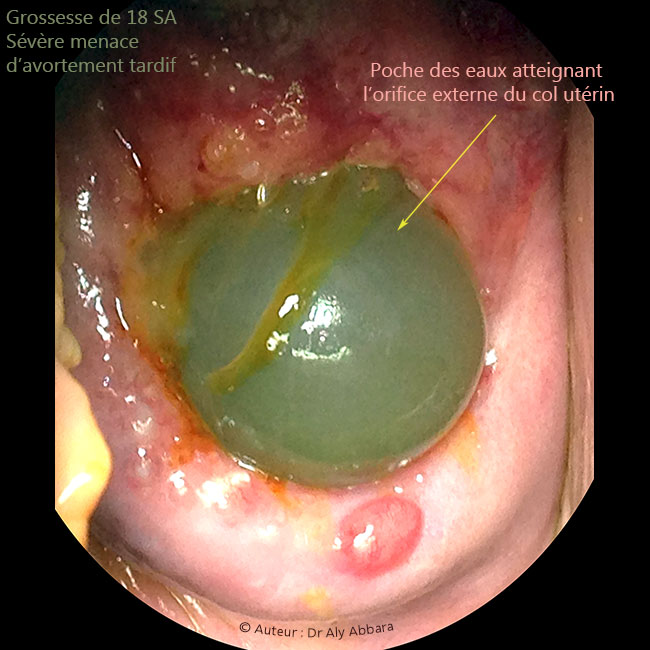

Grossesse de 18 SA - béance du col utérin ; poche des eaux atteignant l'orifice externe du col utérin

Série d'images montrant les aspects échographiques et cliniques d'un col utérin à orifice interne incompétent permettant la protrusion de la poche des eaux dans la totalité du canal cervical pour la laisser atteindre puis dépasser l' orifice externe de col utérin qui est ouvert de 2 cm (au toucher vaginal) sur la totalité de sa longueur.

Il s'agit d'une femme enceinte de 18 SA, ayant dans ses antécédents un accouchement normal au terme de 39 SA sans aucune notion de menace d'avortement tardif ou d'accouchement prématuré lors de cette première grossesse.

Pour la 2ème grossesse en cours, cette incompétence de l'orifice interne du col utérin sévèrement menaçante d'avortement tardif fut découverte fortuitement lors d'une consultation classique prénatale à 17,5 SA, sans contractions ou douleurs abdomino-pelviennes ressenties par la patiente.

Absence de signes cliniques ou biologiques francs pouvant évoquer le diagnostic d'une chorioamniotite.